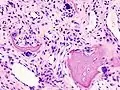

-

Histopathology of osteoarthrosis of a knee joint in an elderly female